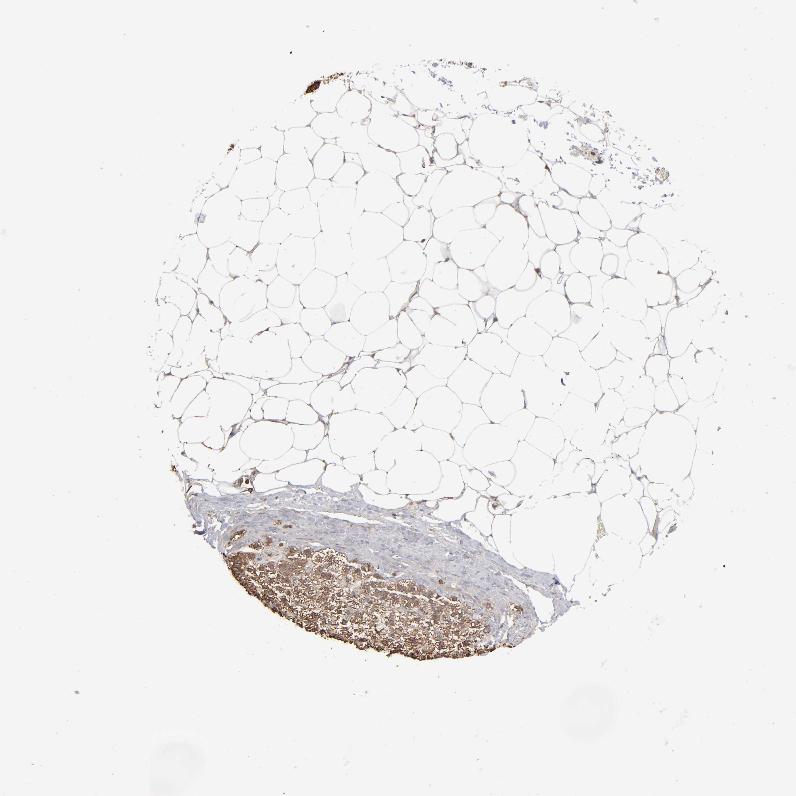

ADRENAL GLAND - Antibody stainingi

Antibody staining in the annotated cell types in the current human tissue is reported as not detected, low, medium, or high, based on conventional immunohistochemistry profiling in selected tissues. This score is based on the combination of the staining intensity and fraction of stained cells.

Each image is clickable and will lead to virtual microscopy that enables deeper exploration of all samples and also displays staining intensity scores, fraction scores and subcellular localization as well as patient and tissue information for each sample.

Antibody HPA008467Antibody HPA041113Antibody CAB002169Antibody CAB076057

Glandular cells HighMediumHighMedium